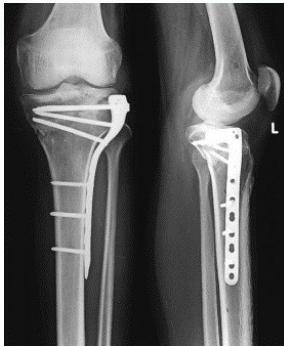

Buttress Plate (T-Plate/L-Plate):

- Indications:

- Lateral or medial tibial plateau fractures

Anatomical Plates with Locked Screws:

- Indications: Metaphyseal fractures

- Advantages:

- Anatomically contoured

- Very good fixation in metaphyseal area and osteoporotic bone